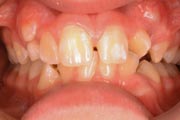

Crowding

Before